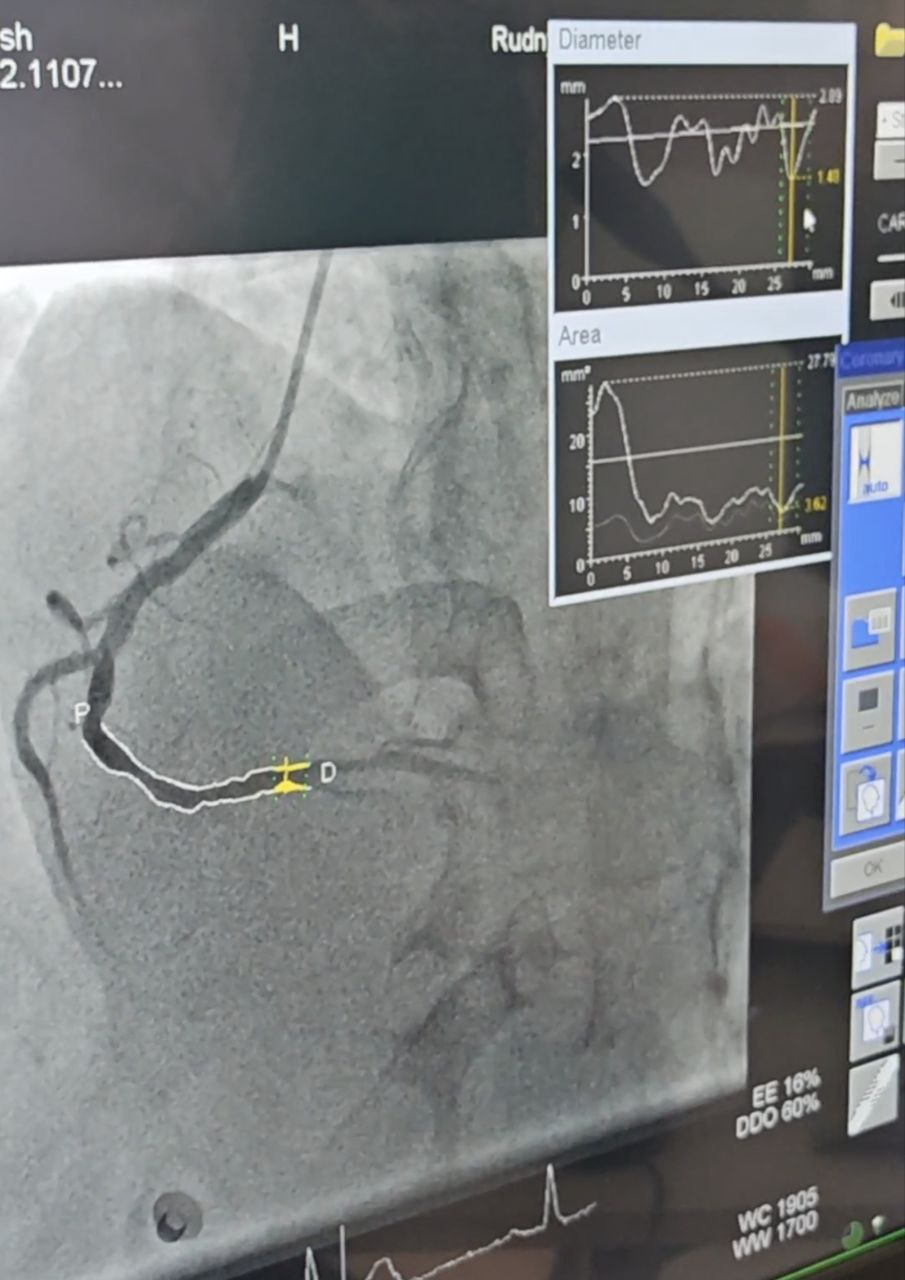

В Рудненской городской многопрофильной больнице долгожданное событие: запущена в работу ангиографическая система «Siemens Artis zee FLOO». Это современное оборудование приобретено за счет местного (областного) бюджета на сумму 791 800 000 тенге.

Современная ангиографическая система предназначена для проведения коронарографии (исследование сосудов сердца), церебрографии (исследование сосудов головного мозга), проведения внутрисосудистых операций кардиологическим и нейрохирургическим больным, также операций на периферических сосудах. Этот спектр медуслуг относится к высокотехнологичной медицинской помощи. Также в условиях ангиографической лаборатории можно проводить локальную остановку кровотечений и кровоснабжения опухолей, «закрыв» тот или иной сосуд.

-Если объяснять максимально просто, то это рентгеновская установка, в сосуды вводится специальное рентгенконтрастное вещество, которое, когда мы включаем ангиографическую установку, показывает нам ту точку, которую мы хотим увидеть. В чем отличие новой системы? Качество визуализации лучше. Соответственно, доктор может провести более качественную работу и увидеть те нюансы, которые он не увидит на предыдущих версиях ангиографа. Плюс для персонала, работающего здесь, в том, что лучевая нагрузка гораздо ниже, - рассказал рентген-хирург* РГМБ Азамат Ержанов. – Именно такой аппарат единственный в Рудном, два аналогичных установили в Костанае.